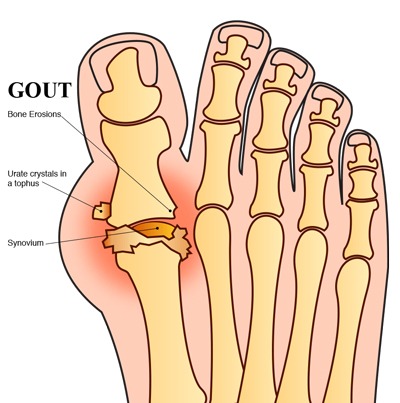

بیشتر بخوانید »علایم و راههای پیشگیری از نقرس

نقرس چیست نقرس بیماری شایع در مردان است و در زنان بعد سن یائسگی بروز میکند. در واقع نقرس بیماری است که در اثر رسوب اسیداوریک در بافتهای بدن، مفاصل و کلیهها اتفاق میافتد. هنگامی که غلظت اسید اوریک در خون از حدی بالاتر میرود، به کریستال تبدیل میشود و رسوب میکند. نقرس بیماری شایع در مردان نقرس بیماری میانسالی …